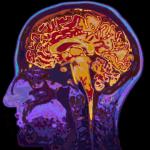

Roger Ailes, one of the founders of Fox News, died from an intracranial hemorrhage (bleeding inside the skull) after falling and hitting his head. Though the bleeding was exacerbated by the fact Mr.